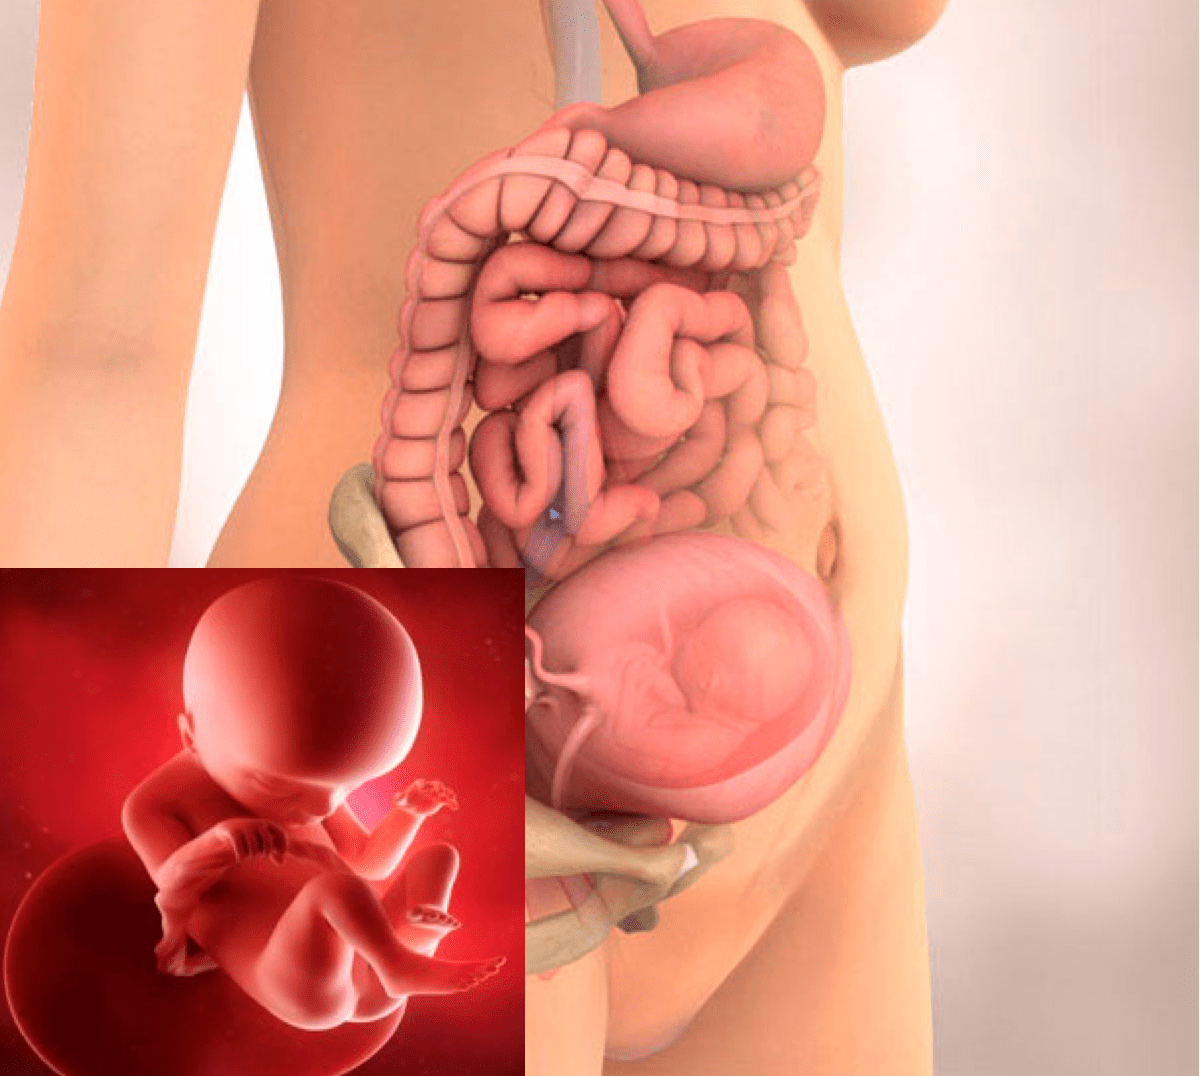

Расположение плода на 15-й неделе беременности: фотографии и иллюстрации